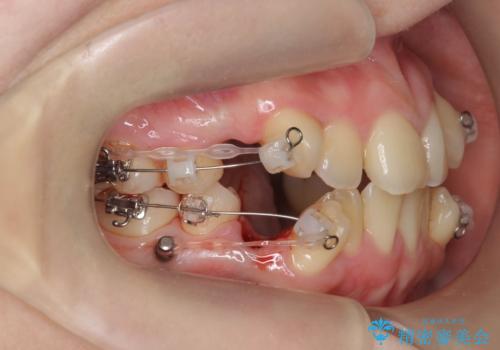

歯並びのせいで歯ブラシがしづらい マルチブラケットを用いた抜歯矯正

- 歯並びのがたつきにより歯ブラシがしづらく、今後虫歯になってしまう不安から、矯正治療を希望されて来院されました。

歯を並べるにはスペースが不足しているため、小臼歯の抜歯を4本行うマルチブラケット矯正による治療を計画します。

治療後は非常に歯ブラシがしやすくなったと、治療結果に満足いただくことができました。